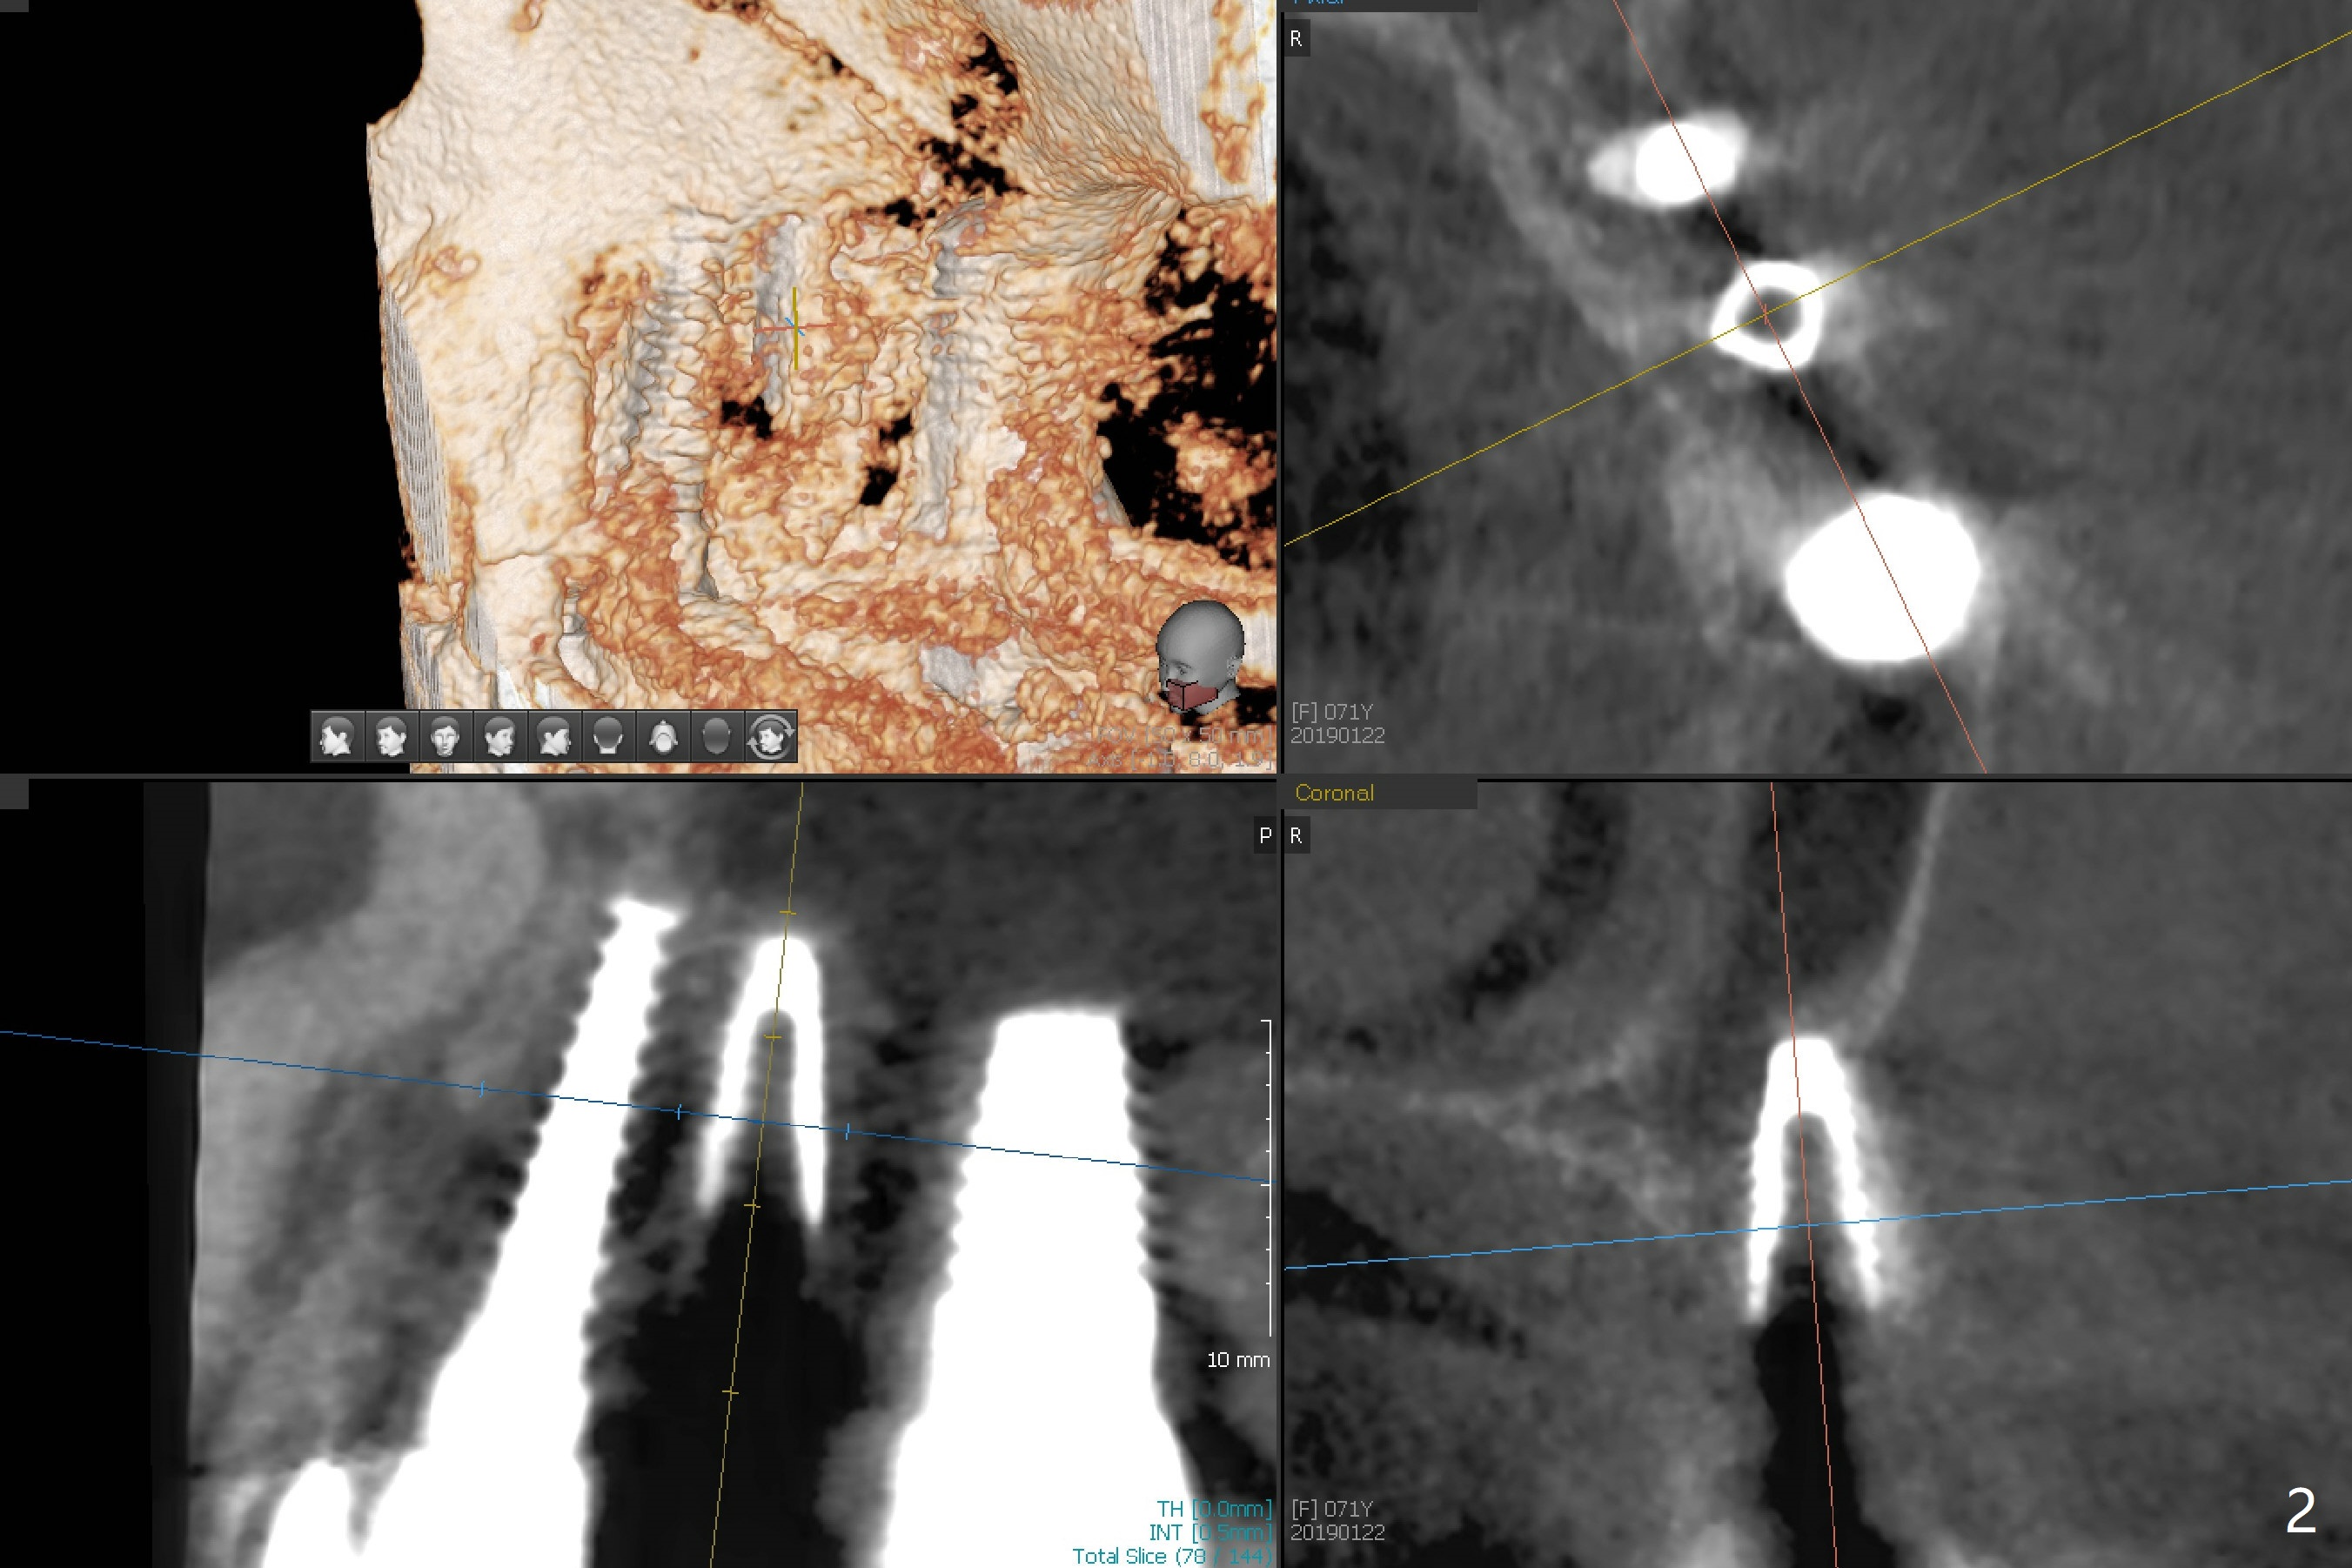

After osteotomy with guide and 2.2 mm drill for ~ 4 mm at #14, a bone expander (1.3/2.3 mm) is used free hand for sinus lift for 12 mm (from the gingival margin, Fig.1; a 10 mm long implant is planned). Following the next expander (1.7/3.1 mm) for the same depth with binding, the sinus membrane is suspected to have perforated. A piece of Osteogen Plug is inserted into the osteotomy as deep as possible with the purpose to repair the sinus membrane (no bone graft being used), followed by placing a 3.5x8.5 (instead of 10) mm implant with insertion torque ~ 25 Ncm (Fig.2,7-9, CT). As compared to preop CT (Fig.4-6), the previously grafted bone is lifted into the sinus by the bone expanders and the implant (Fig.7*). At the same time, the grafted bone has been condensed and pushed buccally (B) (Fig.8,9 *). A 4x6 mm healing abutment is inserted (Fig.3). There is crestal bone loss 6 months postop (Fig.10). Buccal plate atrophy involves the 3 implants in a row (Fig.11). The crown is loose 1 year 8 m post cementation (Fig.12). After proximal reduction, the crown/abutment rotates and sits down substantially (Fig.13). Since the crown is extremely long, it cannot be seated together with the abutment. The latter is seated with X-ray confirmation before proximal reduction of the crown (Fig.14).